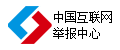

同時,由于現在的B超機很多也帶有VGA接口,用專業的VGA圖像采集采集的圖像質量非常高,在行業的應用中也得到用戶的普遍認可。如下圖所示,根據客戶要求抓取客戶計算機VGA屏幕輸出的CT以及X光機圖片,其中使用的采集設備是維視圖像研發生產的MV-VGA200采集卡,采集分辨率1024*768,刷新率60HZ。采集的圖像細節好,字跡清楚,對比度高,便于醫生辨別病變,用于光片輸出大屏顯示以及醫療圖像處理分析。

上述VGA采集卡的應用實例中,頭部是CT影像、胸部是X光影響,這些用于醫療工作站的原始采集設備也是維視圖像研發生產的MV-M1000/M2000高端黑白采集卡,該系列產品已經廣泛用于采集高頻的CT、X光機、核磁等非標準醫療設備中。維視圖像有多年的醫療圖像采集解決方案的提供經驗,可為用戶提供優質的視覺解決方案。